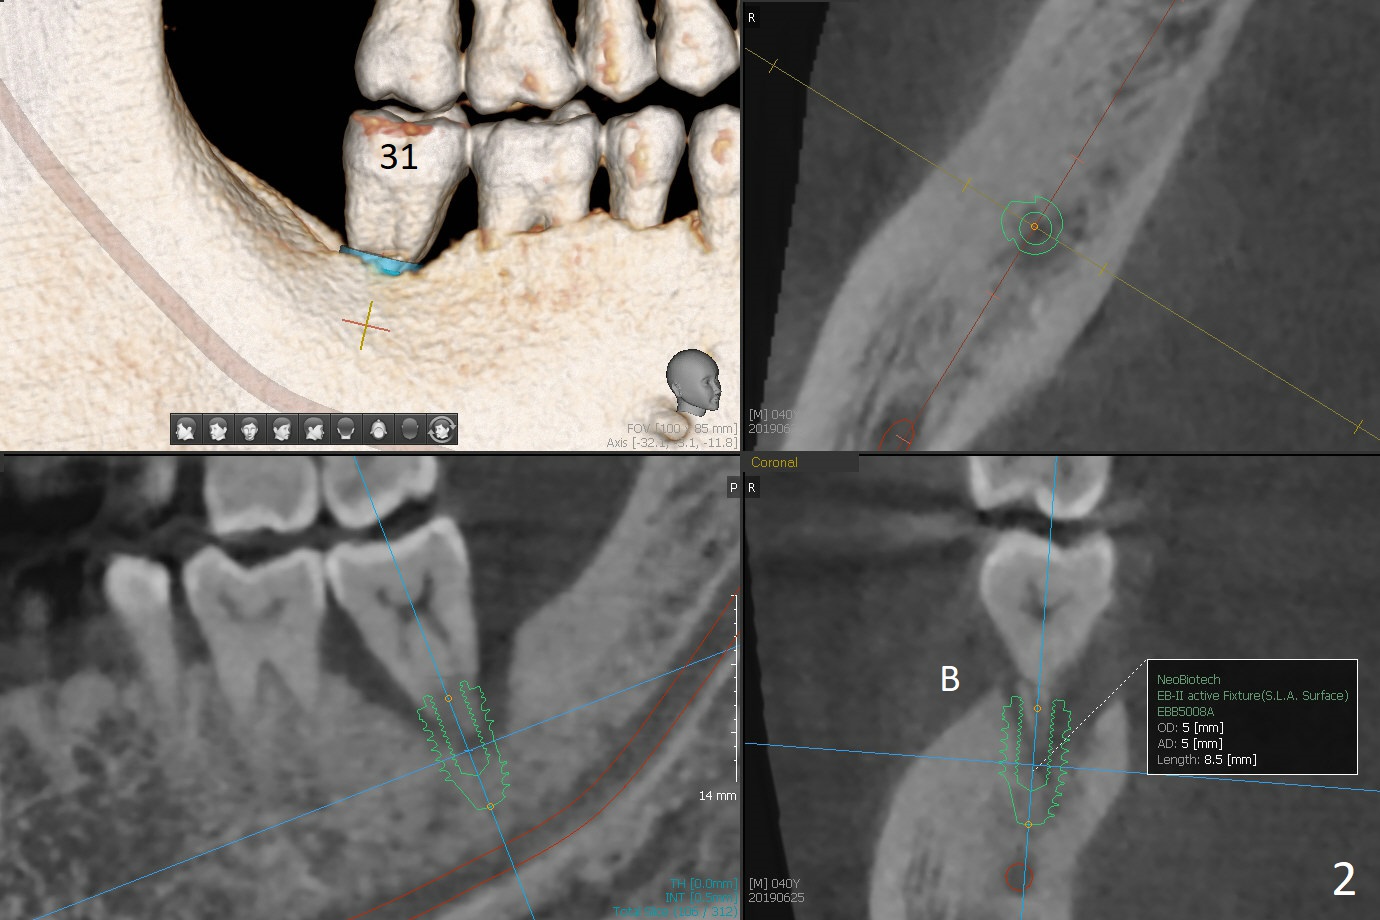

A 40-year-old man (smoker, 1ppd) is concerned about #31 mobility (Fig.1). Gross debridement is finished in his 1st appointment, while impression is taken for guide in his 2nd one. SRP has been scheduled for lower right quadrant with #31 extraction and immediate implant (Fig.2). The tooth #17 extraction will be postponed. The extraction may lead to mobility of the tooth #18, although SRP for the other 3 quadrant will be scheduled 1 week post #31 surgery. Smoke reduction is encouraged. When the crown is delivered at #31 one year later, the tooth #18 is loose (Fig.3) with lingual fistula. Since bone loss is more severe lingual (L *), a 5x10 mm immediate implant will be placed buccal (Fig.4). The tooth #17 will be kept as a distal stop for guide and extracted after #18 implant placement. Bone loss at #18 is more severe with mobility 15 months later; a shorter implant will be placed (Fig.5). After local scaling & root planing of the distal surface of #19 and application of Endogain, place sticky bone (red circle). Insert Collagen or Osteogen Plug in the #17 sockets.